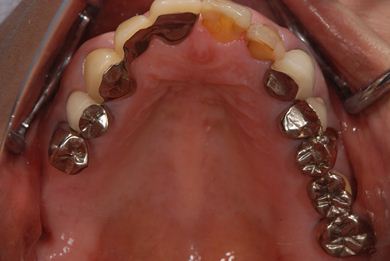

治療後

• 治療後